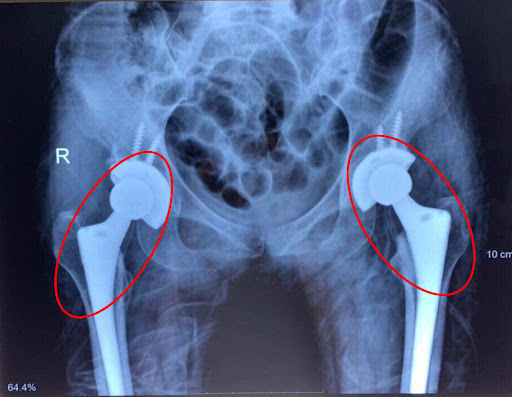

Phẫu thuật thay khớp háng

Mục đích của phương pháp phẫu thuật này là loại bỏ khớp háng bị tổn thương và thay thế bằng khớp nhân tạo, từ đó giúp bệnh nhân cải thiện khả năng hoạt động, đồng thời dễ dàng tái hòa nhập với cuộc sống thường ngày.

Thay khớp háng được phân loại thành hai dạng gồm:

- Thay một phần khớp háng: được chỉ định khi lớp sụn bị bào mòn và khớp chỉ bị tổn thương một phần.

- Thay khớp háng toàn phần: chủ yếu dành cho những trường hợp như sau: